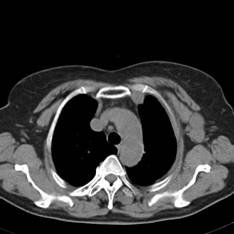

典型病例1:患者鞠xx,女,68岁,住院号:488141,因左胸痛1月余入院。2015年3月31日胸部增强CT示:左肺下叶2.5cmx2.8cm占位,左侧第三前肋骨溶骨性转移、形成厚约3cm肿块,左侧腋窝淋巴结2.1cmx4.1cm及前纵膈淋巴结转移。患者于2015年4月1日经CT引导下穿刺活检、病理证实为左肺下叶腺癌。于2015年4月5日对其采用125I放射性粒子置入治疗。治疗3个月随访,患者胸痛缓解,左肺下叶原发病灶消失,粒子聚集;左侧第三前肋骨基本恢复正常形态;前纵膈淋巴结消失,粒子聚集;左侧腋窝淋巴结缩小2/3。目前患者生活质量良好,可从事一般家务劳动。

术前CT片: